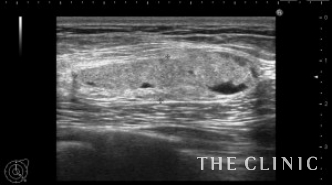

黒いオイル成分が増えてきましたので、太めの注射針で穿刺吸引しました。

除去した脂肪です。

豊胸後間もない時期のしこりの性状は時間の経過とともに変化する場合もあります。

今回は注射針で治療することができ、患者さんにも喜んでいました。